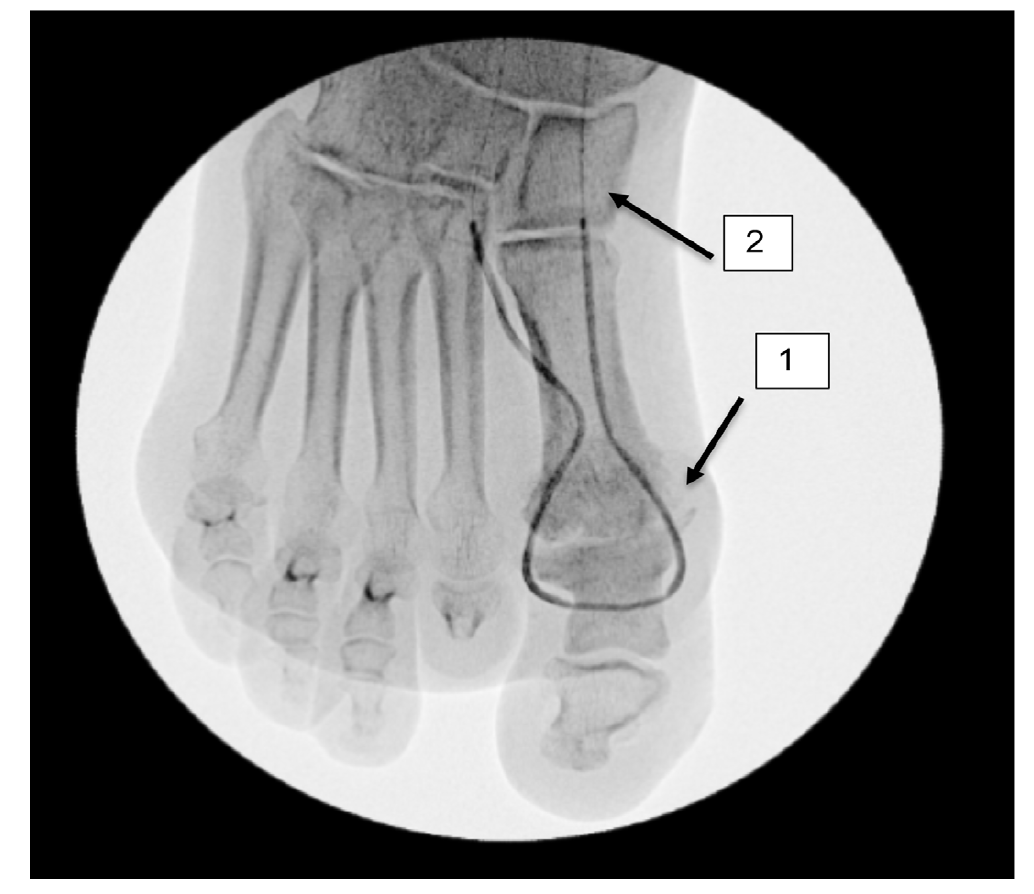

However, the entirety of the medial plantar artery (MPA) distribution was chronically occluded shortly after take-off (Figure 2E and Figure 2F). Super-selective angiography revealed chronic total occlusion of the medial branch of the first common plantar digital artery arising from the first plantar metatarsal artery (Figure 2G). Angiography also revealed an occluded accessory branch arising medially from the superficial branch of the MPA.

The anatomy of the arteries supplying the hallux is complex, with variants being common. In this patient, an atypical accessory branch arising from the superficial branch of the MPA was present. While the arterial anatomy of hallux-supplying arteries and its corresponding variants are not readily discussed in recent literature, certain textbooks do depict an accessory branch arising from the superficial branch of the MPA.2 The accessory branch of this patient, in particular, communicated with the first dorsal metatarsal artery arising from the DPA (Figure 2F) and the superficial branch of the MPA communicated with the medial branch of the first common plantar digital artery arising from the LPA (Figure 4C). In general, using the angiosome concept, the blood supply to the hallux consists of 3 main avenues: (1) the first dorsal metatarsal branch arising from the DPA; (2) the plantar digital arteries arising from the first plantar metatarsal artery, which is a branch of the LPA; and (3) the superficial branch of the MPA.3,4 The latter 2 sources of blood supply were absent in this case.